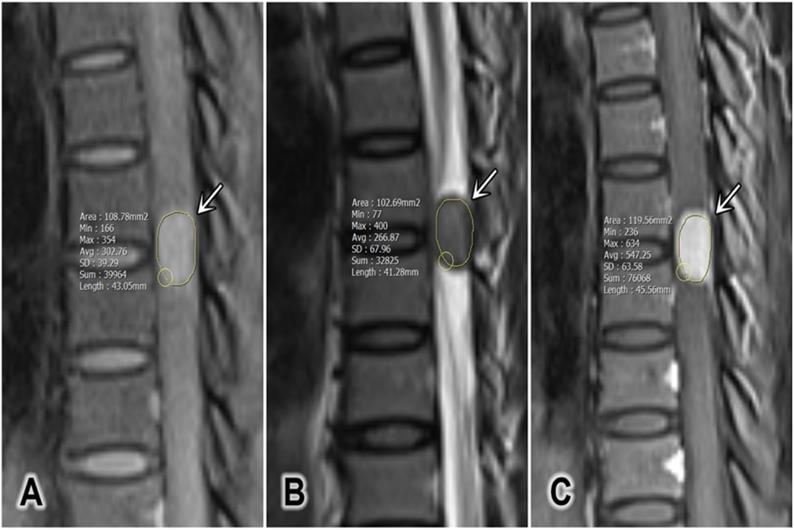

The tumor size was defined as the average of the anterior-posterior diameter and the greatest horizontal diameter on a single T2W slice [2]. The longitudinal spinal location of the tumor was defined as cervical, thoracic, lumbar, or sacral. The horizontal location of the tumor was defined as anterior, posterior, or lateral. The signal intensity (SI) of the tumor on T2W was measured, and maximum (T2max), minimum (T2min), and mean (T2mean) values were recorded. Pre-contrast and contrast-enhanced T1W (T1CE) SI values were measured, and the maximum (T1max and T1CEmax), minimum (T1min and T1CEmin), and mean (T1mean and T1CEmean) values were recorded in defined regions of interest (ROIs; Figure 1). The ROIs were hand-drawn and set with surrounding tumors on sagittal plane on T1W, T2W and T1CE to obtain the similar size of the ROI and to compare the tumor components on different sequences. At the largest area of the tumor, the ROI should cover at least two-thirds of the tumor diameter and should not contain any other surrounding structures (cerebral spinal fluid, bone, or ligamentum flavum). The SI for fat (SI fat) was determined by obtaining the mean value from three circular regions (covering 20-60 mm2) on the posterior side of the spinous process and both side pedicles. All of these values should be measured on the same slice, corresponding with the region in which the tumor size is the largest (Figure 2) [15]. The tumor to fat SI ratio on T2W (rTF) was calculated as SI tumor/SI fat.

Figure 1

A representative region of interest defined for a tumor (white arrows). (A) Sagittal T1-weighted image, (B) sagittal T2-weighted image, and (C) sagittal contrast-enhanced T1-weighted fat-saturated image.